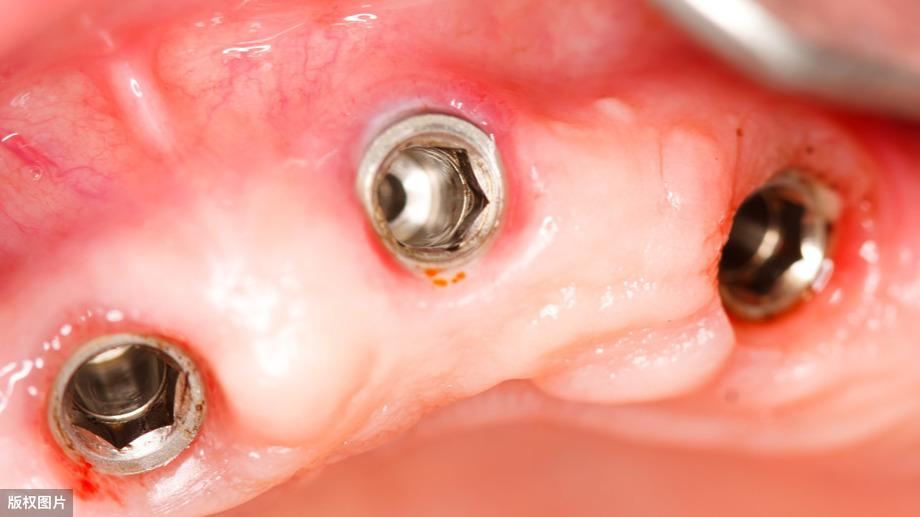

面對(duì)滿口缺牙,現(xiàn)在更多口腔醫(yī)院會(huì)給出all-on-4的種植方案,All―on―4種植技術(shù)是源自歐美的先進(jìn)口腔種植技術(shù),主要針對(duì)全口無(wú)牙或者半口無(wú)牙的情況下,只利用4-6顆種植體固定半口牙橋,然后在種植體的基臺(tái)上安裝“拱形連橋”牙冠,從而完成整口牙的口腔種植修復(fù),這對(duì)于牙槽骨骨量不足的患者可以說(shuō)是一大喜訊。

由于all-on-4全口種植牙技術(shù)的特點(diǎn),導(dǎo)致全口種植牙費(fèi)用大大減少,單排牙齒缺失只需要種植4個(gè)種植體即可支撐半口的牙橋,這樣,讓種植牙費(fèi)用節(jié)省了70%左右。

同時(shí),如果長(zhǎng)期缺牙,多數(shù)種植牙技術(shù)都是需要植骨的,等待牙槽骨長(zhǎng)好后,才能進(jìn)行種植修復(fù),而all-on-4全口種植牙技術(shù)大大改良了這點(diǎn),多數(shù)情況下無(wú)需植骨,讓更多的高齡患者也可以接受種植牙。

這一位老先生則選擇了All-on-4種植技術(shù),即拔即種,上下頜分別種植4個(gè)植體就完成了全口牙齒修復(fù),費(fèi)用降低了不少,而且創(chuàng)傷小,恢復(fù)快。